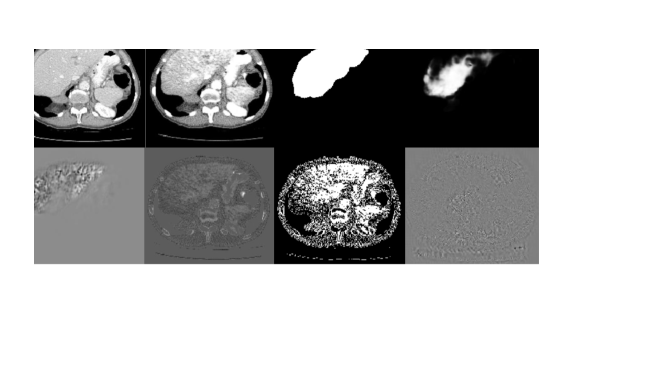

Figure 2: Gradient maps of different losses. The first row shows ground truth NDCT image 𝐱superscript𝐱\mathbf{x}^{*}, the output of the denoising network 𝐱^^𝐱\hat{\mathbf{x}}, the segmentation ground truth, and the out put of the representative model incorporated in the task-oriented loss. The second row shows the map of L𝐱^𝐿^𝐱\frac{\partial L}{\partial\hat{\mathbf{x}}} of 4 different losses.

To analyze how the task-oriented loss complements other commonly used denoising losses, we examine the similarities and differences between their partial derivatives with respect to the denoiser’s parameters θGsubscript𝜃𝐺\theta_{G}. Specifically, we compare the task-oriented loss to MSE loss LMSEsubscript𝐿𝑀𝑆𝐸L_{MSE}, L1subscript𝐿1L_{1} loss, and perceptual loss (Lpsubscript𝐿𝑝L_{p}). For brevity, we use 𝐱^^𝐱\hat{\mathbf{x}} to represent G(𝐱)𝐺𝐱G(\mathbf{x}). Then we have

where f()𝑓f(\cdot) denotes the network used in the perceptual loss. In Eq. 6, \vmathbb1[]=1\vmathbb1delimited-[]1\vmathbb{1}[\cdot]=1 when 0\cdot\geq 0 and \vmathbb1[]=1\vmathbb1delimited-[]1\vmathbb{1}[\cdot]=-1 when <0\cdot<0. From Eqs. 4-7, we can see that the partial derivatives of all these four losses share the same term of 𝐱^/θG^𝐱subscript𝜃𝐺\partial\hat{\mathbf{x}}/{\partial\theta_{G}}. The differences between these loss functions lie only in the other part of the derivatives, denoted by L/𝐱^𝐿^𝐱{\partial L}/{\partial\hat{\mathbf{x}}}. For intuitive understanding, Fig. 2 visualizes the values of L/𝐱^𝐿^𝐱{\partial L}/{\partial\hat{\mathbf{x}}} calculated on an output 𝐱^^𝐱\hat{\mathbf{x}} generated by a half-trained denoiser, i.e., TOD-Net before converging. Liver segmentation is the downstream task in this demonstration. Since the decoder has not been fully trained, the “denoised” image 𝐱^^𝐱\hat{\mathbf{x}} includes many artifacts, which significantly degrade the performance of the downstream segmentation network. The second row shows the differences between the task-driven loss and the other three losses, with the partial derivatives of the task-oriented loss being focused on the liver. Such an attention to the task-related regions steers the denoiser to improve the image quality in these regions. Since the improvements are not for a specific representative network the improvements can enhance various other methods for this task.